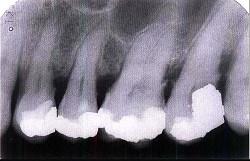

问题 牙槽骨水平型吸收的特点是 ( )

选项 A.是最常见的吸收方式 B.牙槽间隔、唇颊侧或舌侧的嵴顶边缘呈水平吸收 C.牙槽嵴高度有明显降低 D.常形成骨上袋 E.以上均是

答案 E